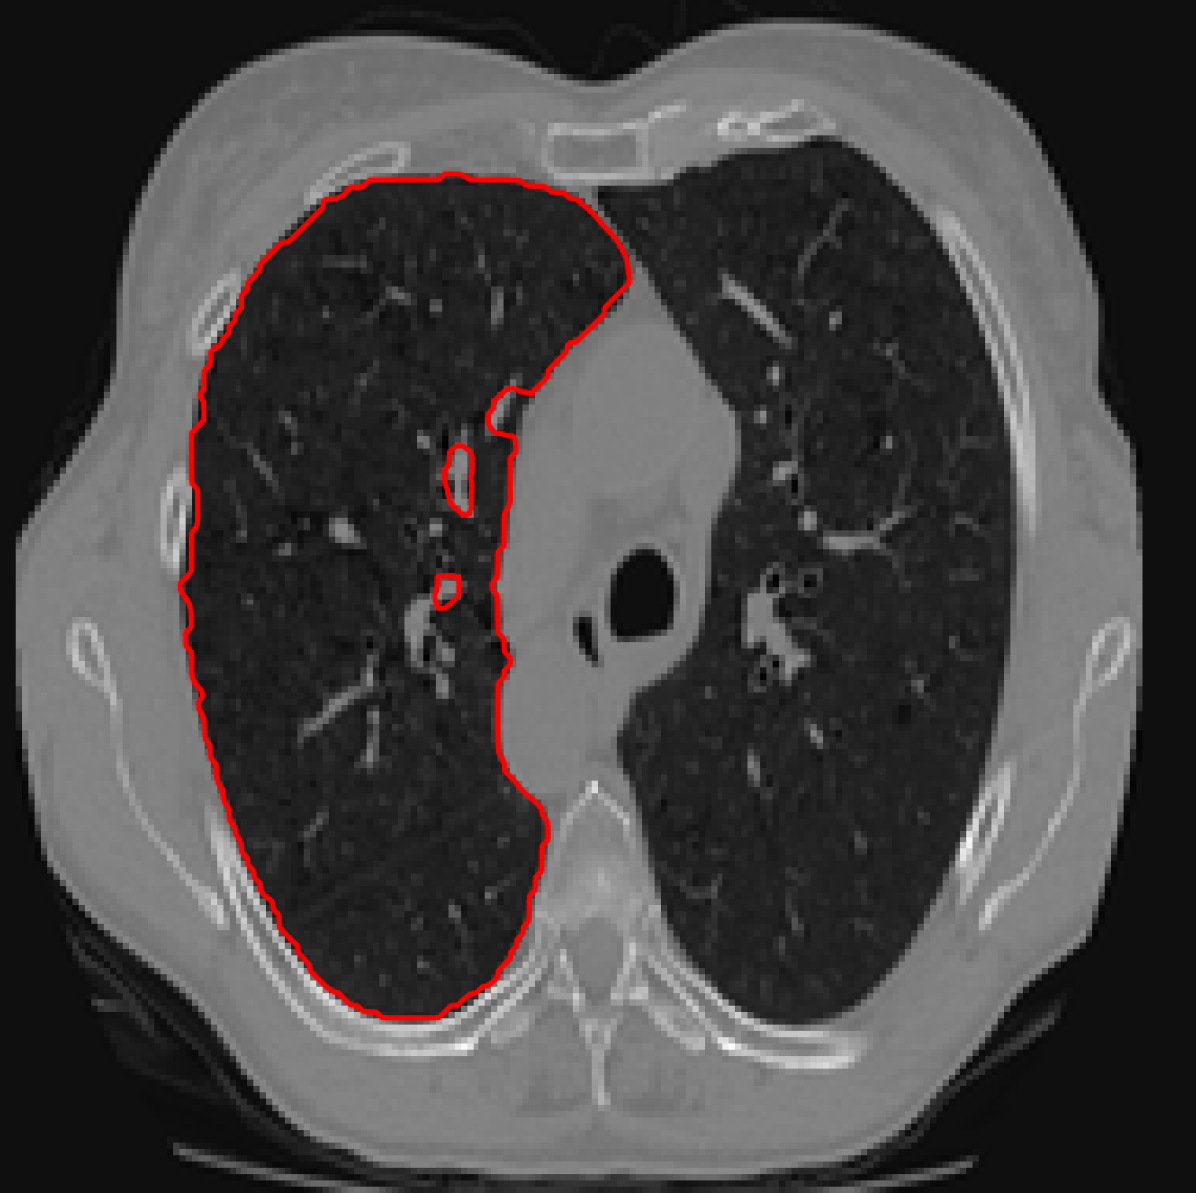

Figure 6: A sample result on the Liver data. We display the input image with the user input \mathcal{M}, the ground truth (GT) and results from the four methods. Moreover, we show comparisons with the model (4) solved in a variational framework with both Total Variation (TV) and Euler Elastica as explicit regularisation, as well as a comparison with the model solved in a Deep Image Prior framework.

Similarly we show some results in Figures 5 and 6 from the LiTS dataset of all the methods. Quantitative results of the 272727 images can be found in 2. Clearly for both datasets, M3 and M4 using the proposed ideas outperform M1 and M2, as well as methods using explicit regularisation (TV and Elastica), and the original DIP method.

In addition, we can also compared with [14] who also used the LiTS dataset. The unsupervised approach trained on over 100010001000 images gave a mean DICE score of 0.6710.6710.671 with a standard deviation of 0.3050.3050.305 on 232232232 validation images. Using our method M4 trained on just 222 images give a mean DICE score of 0.7530.7530.753 and standard deviation 0.2130.2130.213.